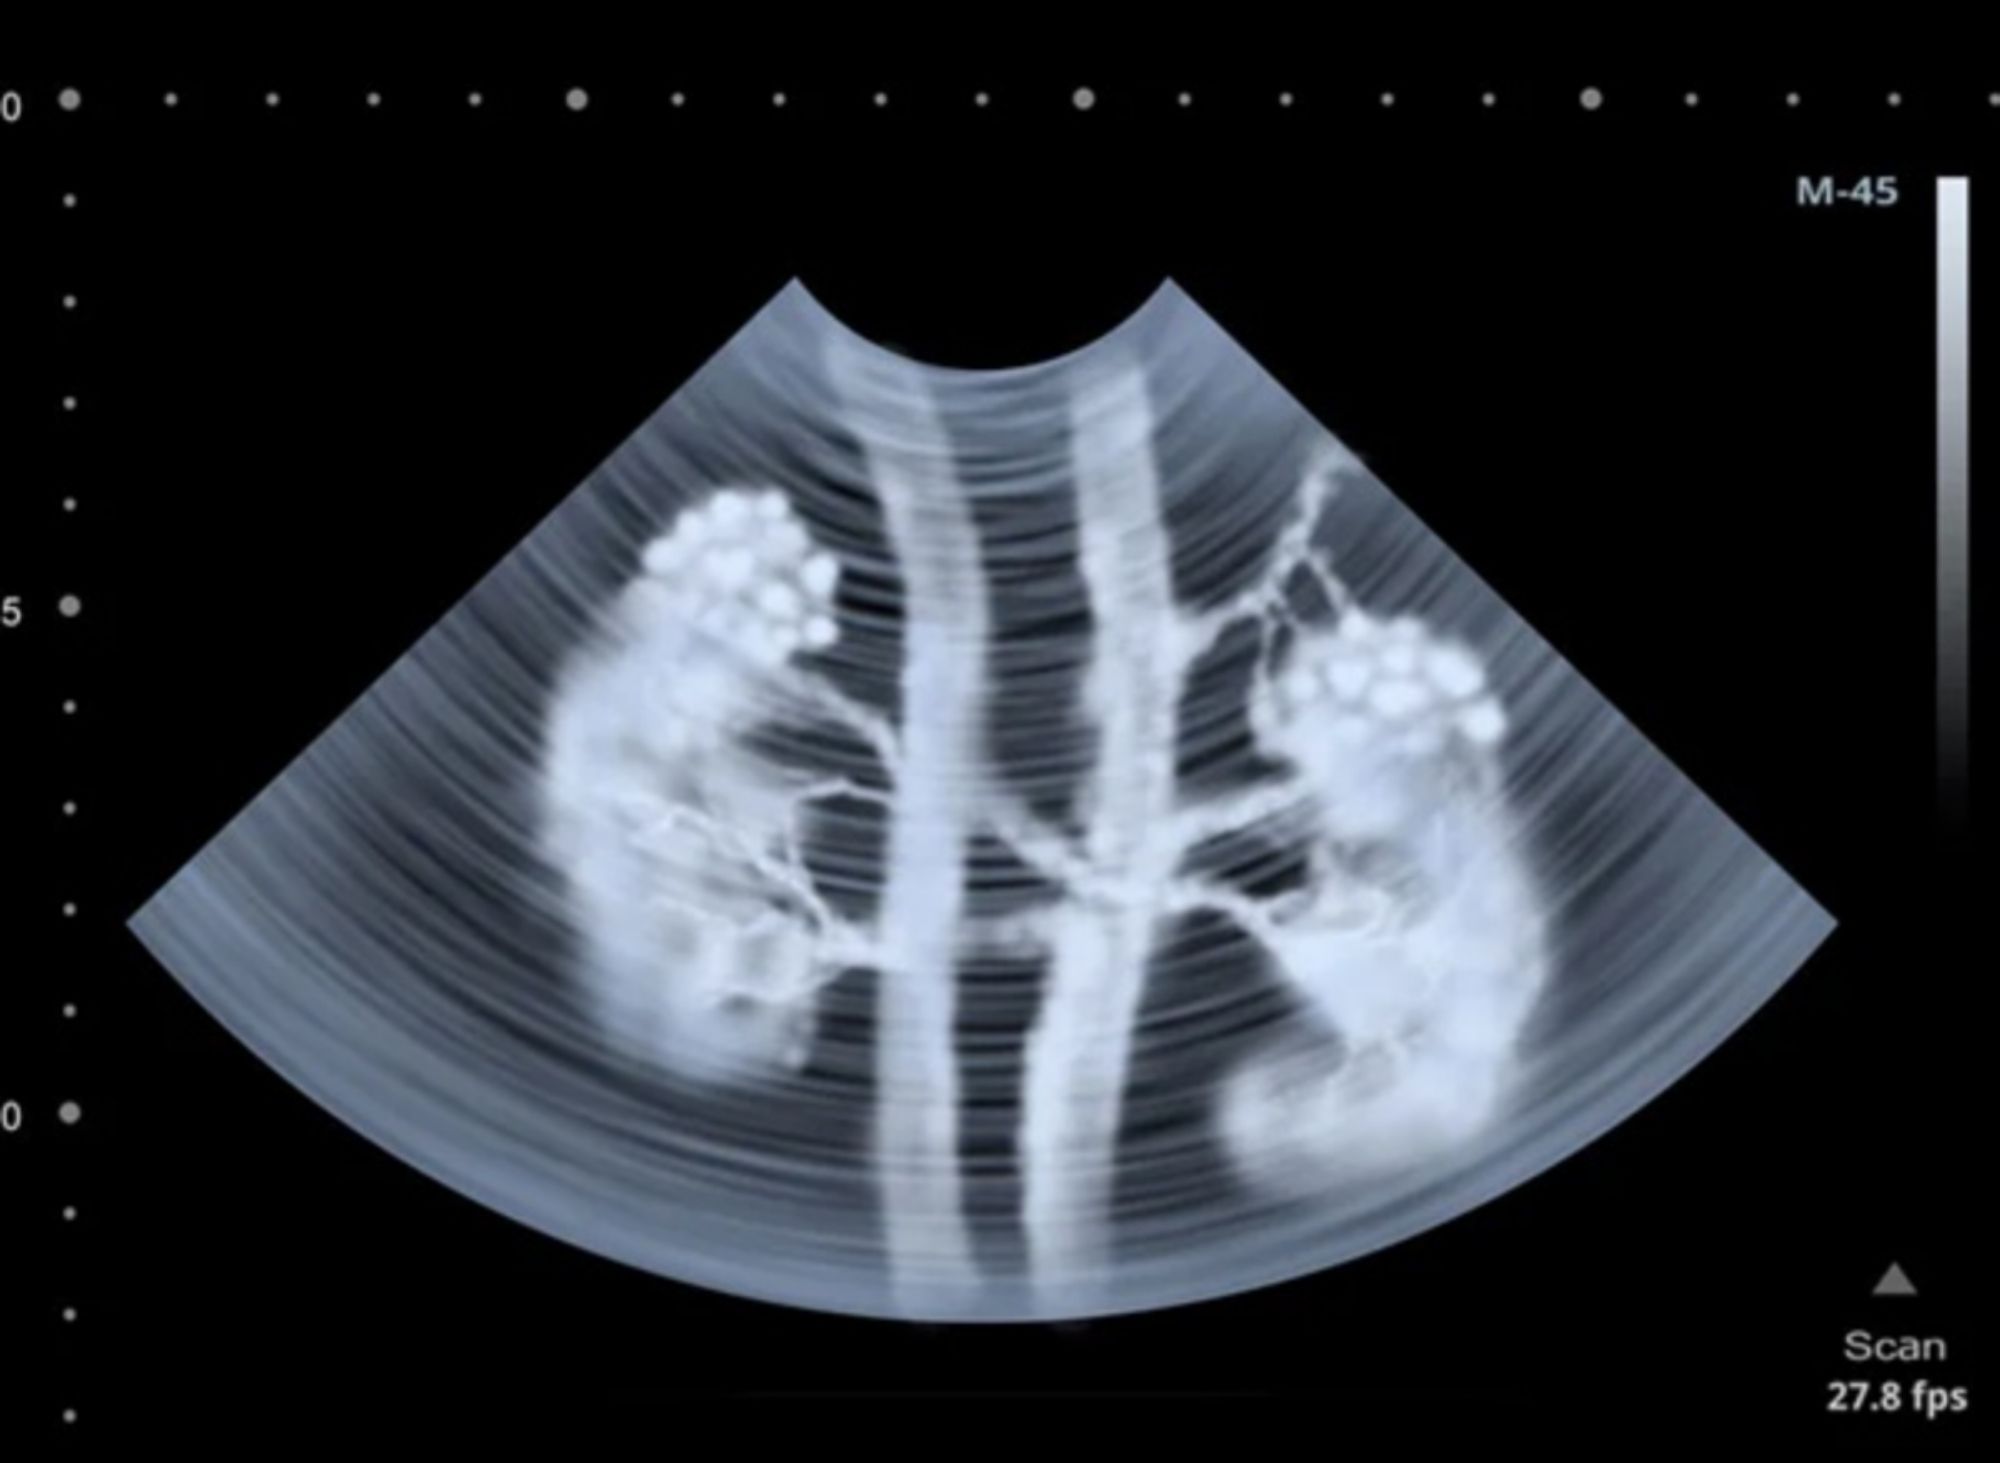

- Dùng DTPA đánh dấu bởi Tc99m, tiêm tĩnh mạch, ghi hình động, giúp đánh giá hình ảnh và chức năng thận (chức năng lọc của cầu thận).

- Pha 1 tưới máu (Flow): Dynamic 1 giây/ hình x 60 hình

- Pha 2 lọc-bài xuất (Excrestion): 60 giây/ hình x 20-30 hình

Xạ hình thận là một kỹ thuật chẩn đoán đơn giản, trong đó ứng dụng y học hạt nhân để kiểm tra tình trạng thận và đánh giá chức năng của thận.